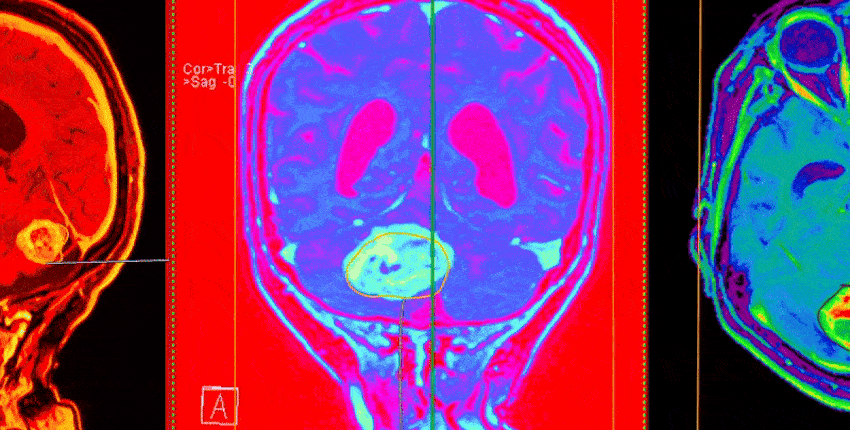

Yu’nun, araştırmanın ortak ilk yazarları Junhan Zhao ve Shih-Yen Lin ile birlikte geliştirdiği model, dünya genelinden toplanan 2.141 beyin patolojisi slaydı üzerinde değerlendirildi. Hem dondurulmuş kesitlerde hem de formalinle sabitlenmiş örneklerde test edilen PICTURE, tümör hücresi yoğunluğu, hücre şekli ve nekroz varlığı gibi kritik özellikleri analiz edecek şekilde tasarlandı.

Model dört ülkedeki beş uluslararası hastanede test edildi. Tüm senaryolarda, mevcut YZ araçlarını ve geleneksel dondurulmuş kesit yöntemini geride bıraktı. Testlerde PICTURE, glioblastoma ile PCNSL’yi %98’in üzerinde doğrulukla ayırdı. Başarı, beş bağımsız uluslararası hasta grubunda da geçerli oldu. Ayrıca model, gliomalar veya lenfomalar dışında kalan 67 merkezi sinir sistemi kanserini de tanımlayabildi.